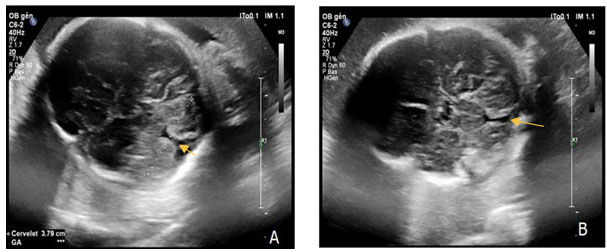

Ultrasound revealed a eutrophic fetus with an estimated fetal weight in the 48th percentile. At the cephalic pole, we observed a complete agenesis of the cerebellar vermis (Figure 1) without other associated brain abnormalities. The ear pavilion was anteverted, detached, and bulging (Figure 2).

Figure 2: Anteverted and bulging ear pavilion. The yellow arrow shows the auricle which is anteverted and deformed by bulging forward. The red arrow shows the cephalic pole.

Anotia or microtia are characteristics of isotretinoin fetopathy. These anomalies are described in 70.8% of cases. Also, stenosis of the external auditory canal is described in more than half of the cases (54.8%) [1],[2],[4],[5]. We described another form of anomaly of the ear pavilion, a normal size but abnormal shaped of ears.

This allows us to conclude that ear anomalies can take different forms in isotretinoin fetopathy. It is therefore necessary to look for exposure when ear abnormalities are detected on antenatal ultrasound.